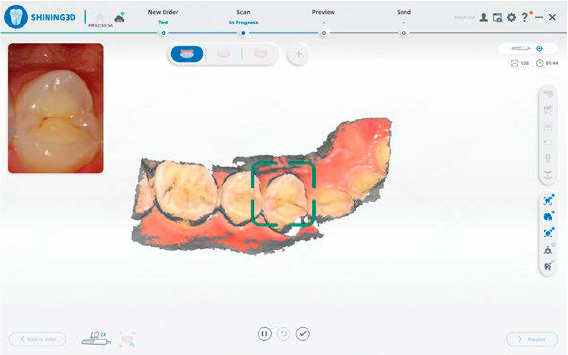

SCANSIONE INTELLIGENTE

Un design pulito e lineare per un processo di scansione più efficiente e senza interruzioni.

INDICATORE DI QUALITÀ

Le aree incomplete vengono evidenziate in grigio, facilitando l’individuazione delle zone da ripassare per una qualità ottimale.

DETTAGLI RAFFINATI

Riproduzione accurata della morfologia e delle preparazioni con fedeltà eccezionale.

AFFIDABILE SU SUPERFICI METALLICHE

Scansioni efficaci anche su restauri metallici e tonalità più scure.